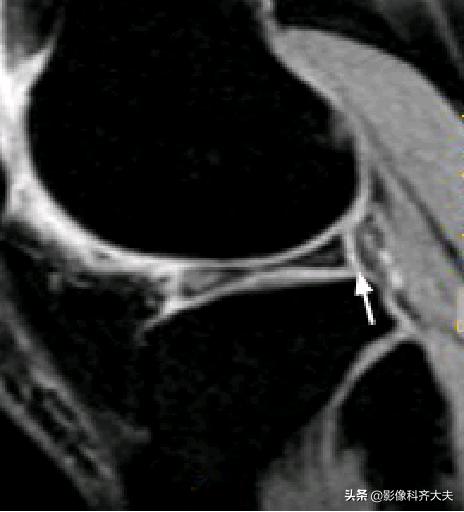

容易误诊为半月板损伤的正常解剖结构

膝横韧带:

腘肌腱腱鞘:

后股板韧带: